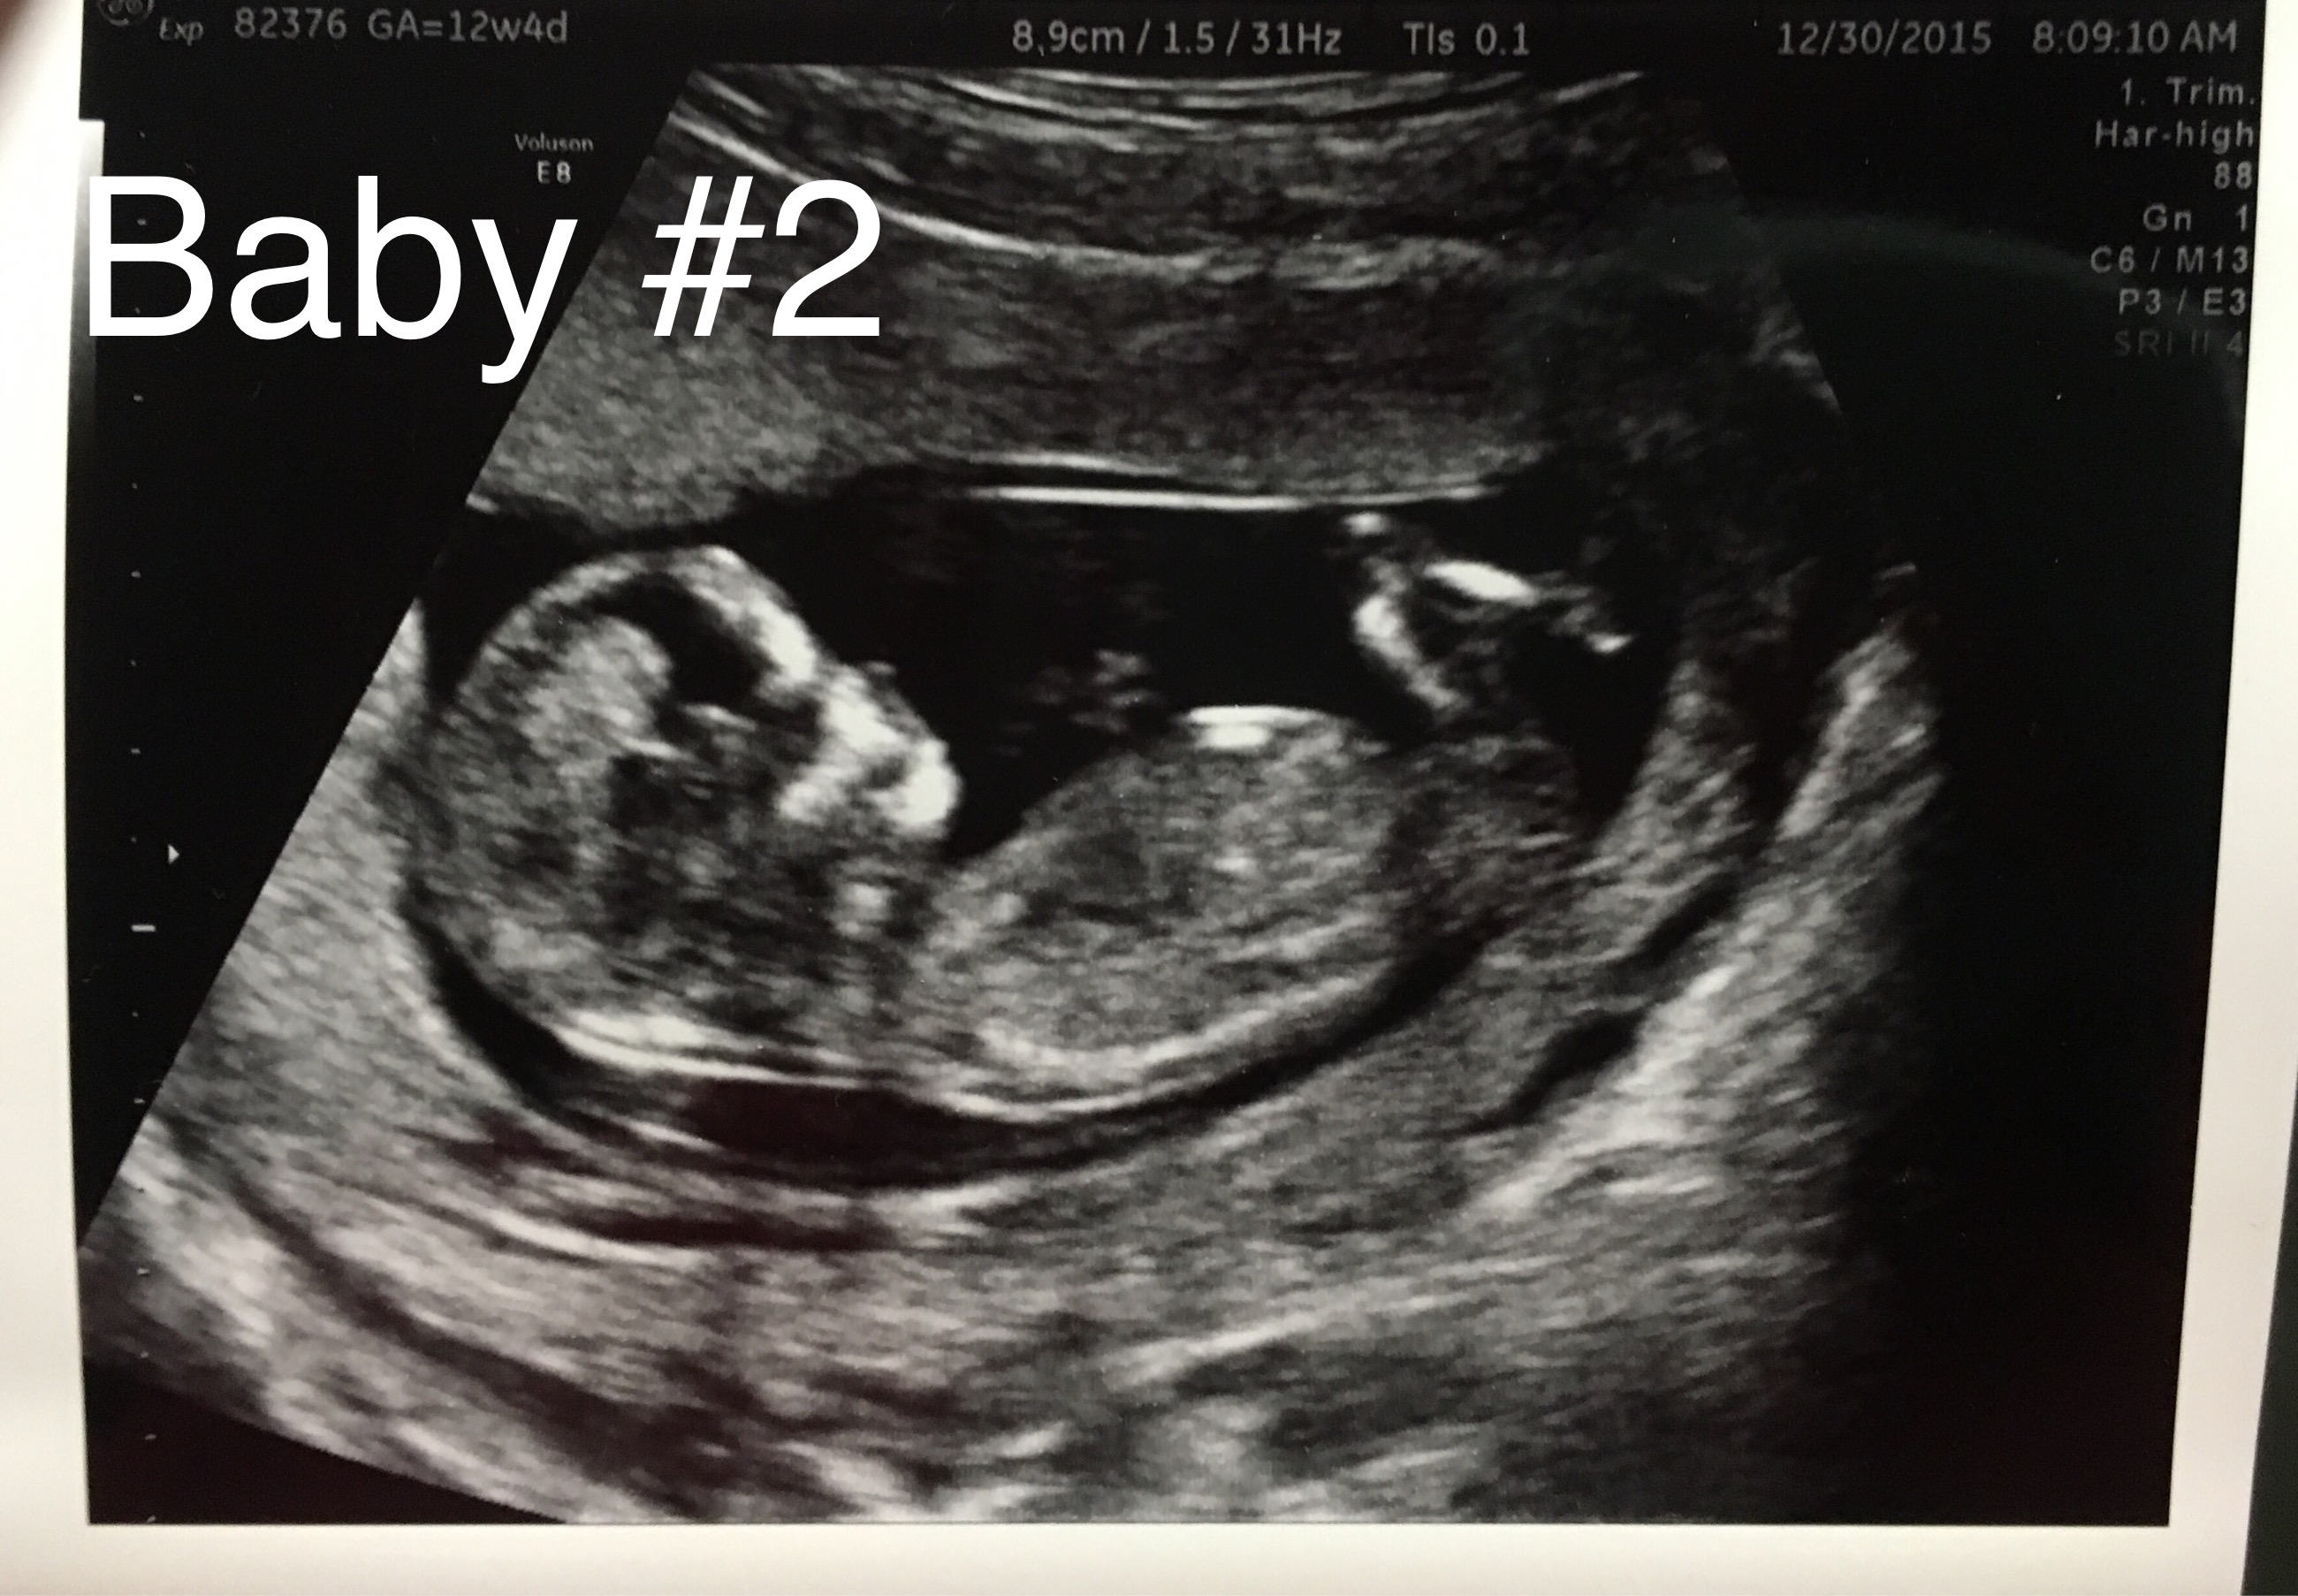

Below are my 12+4 week scan shots, I'm hoping for some gender guesses. Is the nub even visible? I've looked at tons of pics online and can't seem to make out the nub in my pic. I'm kind of thinking boy, this bub looks so much like my DS around the same time (in regards to skull shape, although this baby has a flatter face). I've attached pics of DS as well.

Here is current baby:

Attachment 29169